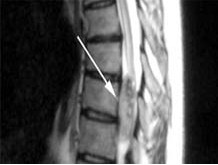

椎管內腫瘤 椎管內腫瘤術中